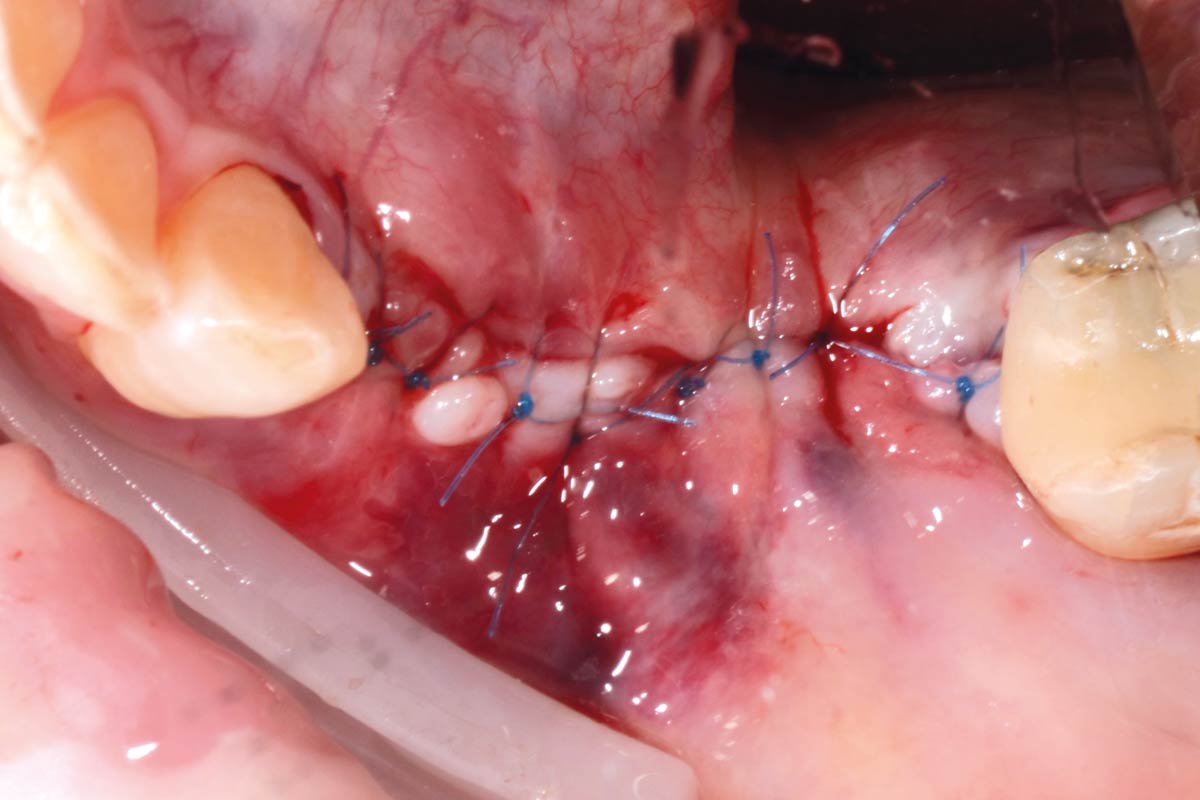

08/29 - Defect closure with non-absorbable PTFE suturesVertical bone augmentation and broadening of attached gingiva using cerabone®, permamem® and mucoderm® - Dr. R. Naimoli